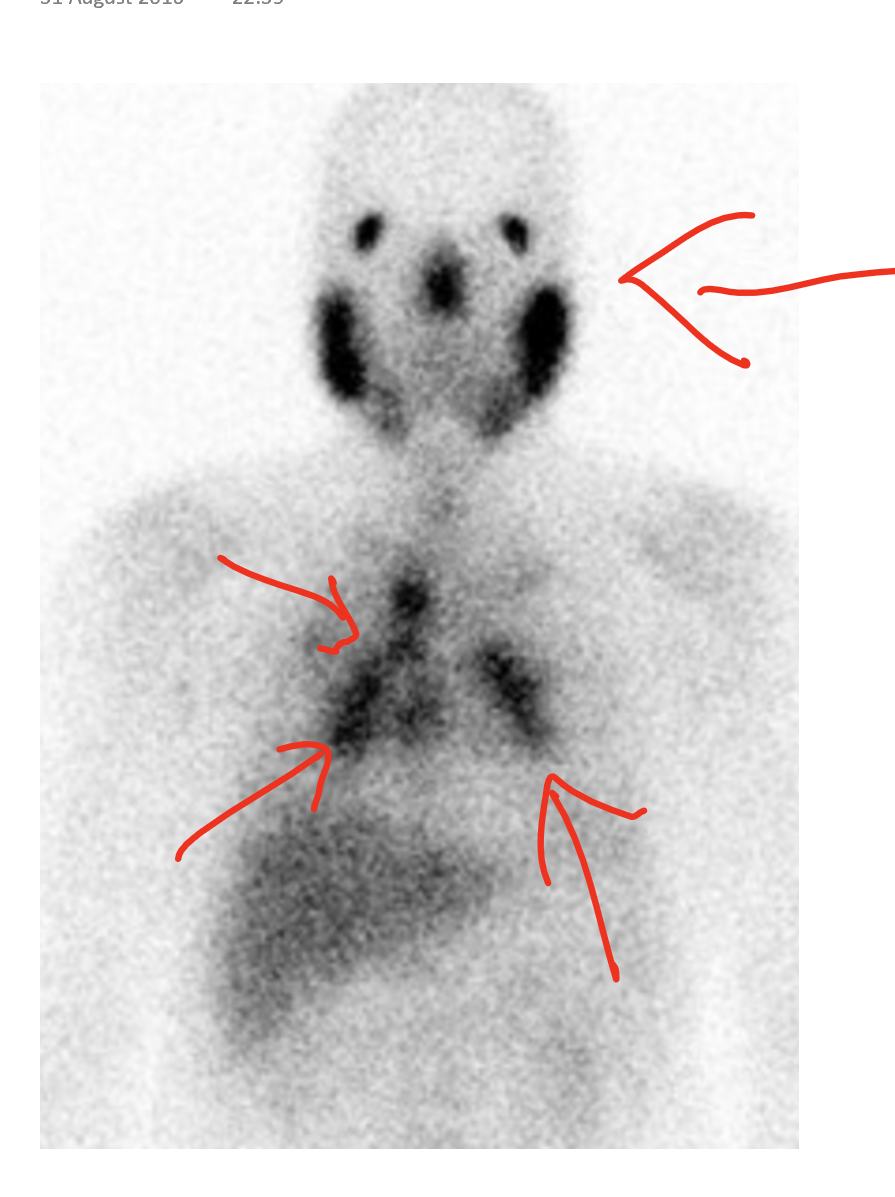

Whole body gallium scan. Notes The first 2 images from the left show What Is A Gallium Scan Test a gallium scan is a study that uses intravenously injectable isotopes of gallium to produce nuclear medicine images. a gallium scan is a test to look for swelling (inflammation), infection, or cancer in the body. a gallium scan identifies the cells that are dividing most quickly in your body. It can find cancer, infection and inflammation in. What Is A Gallium Scan Test.

Whole body gallium scan. Notes The first 2 images from the left show What Is A Gallium Scan Test It uses a radioactive material called gallium and is a type of. It can find cancer, infection and inflammation in the body. a gallium scan is a type of imaging test used in medicine to diagnose infections, inflammation, and certain. It can help detect some cancer cells. a gallium scan is a study that uses intravenously injectable isotopes. What Is A Gallium Scan Test.